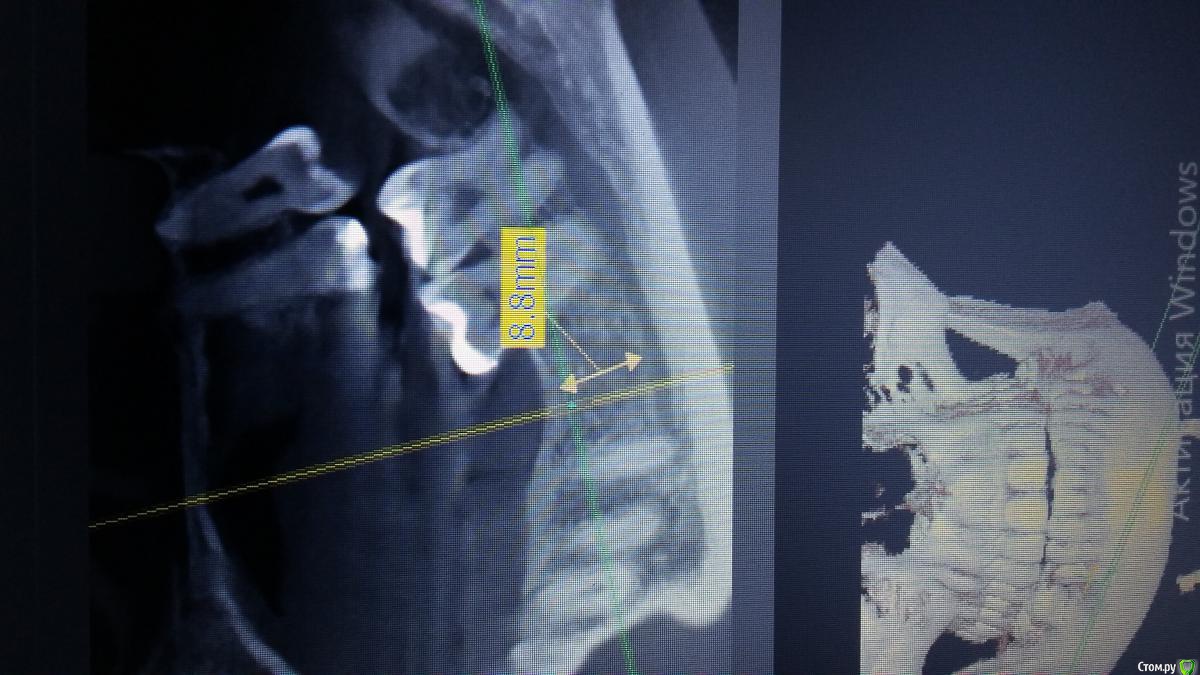

Антон 123 Опубликовано 14 февраля, 2019 Поделиться Опубликовано 14 февраля, 2019 (изменено) Всем форумчанам доброго времени суток. Ставлю импланты недавно,поэтому хочется спросить мнение более опытных коллег. Условия для имплантации следующие зуб 46, до канала9 мм, гребень 7,6мм,угол примерно 20 градусов. Выбрал имплант диаметр 4.5 мм - 8.5 мм длина . Остальные все зубы у пациента есть. Кто что думает? Изменено 14 февраля, 2019 пользователем Антон 123 Ссылка на комментарий

Irouil Опубликовано 14 февраля, 2019 Поделиться Опубликовано 14 февраля, 2019 (изменено) Своеобразно Вы ширину гребня измеряете... 4.5*7, но я бы перезамерил Изменено 14 февраля, 2019 пользователем Irouil Ссылка на комментарий

red_butler Опубликовано 14 февраля, 2019 Поделиться Опубликовано 14 февраля, 2019 а в чем ошибку заметили?я открыт для критики,так как опыта мало,лучше я здесь о своих касяках узнаю,чем в момент имплантации)))мне видится высота 10-10,5 мм, голосую за имплант длиной 7 мм Ссылка на комментарий

Тимур86 Опубликовано 15 февраля, 2019 Поделиться Опубликовано 15 февраля, 2019 (изменено) Мне тоже кажется ~10.5, я бы взял 8.5 Изменено 15 февраля, 2019 пользователем Тимур86 Ссылка на комментарий

Irouil Опубликовано 15 февраля, 2019 Поделиться Опубликовано 15 февраля, 2019 а в чем ошибку заметили?я открыт для критики,так как опыта мало,лучше я здесь о своих касяках узнаю,чем в момент имплантации)))Наискосок как-то, ширина получается больше, длинна - меньше Можно пробовать сверлиться на 8.5, но конус же, будете глубить 1-1.5 мм, вплотную к каналу. В случае не дай бог каких разбирательств шансы оказаться крайним выше Судя по объёмам альвеолярного гребня челюсти у пациента небольшие, нагрузки тоже пропорционально, семёрка должна работать нормально Ссылка на комментарий